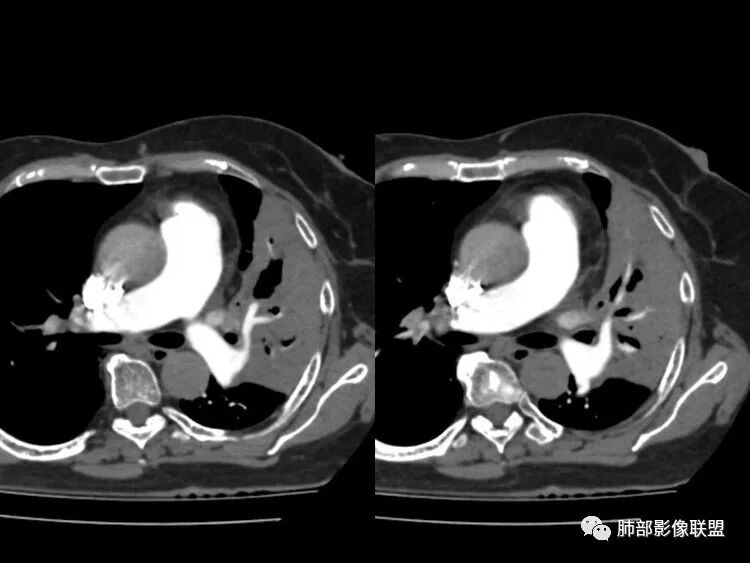

患者近期胸闷气促,D2高,低氧血症,肺动脉干增宽,确实需要警惕肺栓塞,可以做个CTPA排除一下。一元结核不太好解释主诉

南边:这个是左上肺基本没啥功能所致吧肺动脉粗了尘缘:晨读:一、肺栓,CTPA去证实,这个一定有的,二,结核?这个不一定是,也不一定有结果,3、间质性肺水肿,这个应该有,但结果不一定能体现出来。综上:考虑肺栓塞伴间质性肺水肿,结核待排。

影像特点支持结核。气促、左上肺病灶似乎不能解释I型呼吸衰竭加上D—二聚体明显升高、肺动脉干增粗,临床需要想到二元可能:肺结核合并肺栓塞可能,需要完善CTPA明确有没有肺栓塞,因为急性肺栓塞是急危重症。

2.纵隔左移。肺动脉增宽。

D-二聚体升高,肺动脉成像等明确患者肺栓塞的存在!